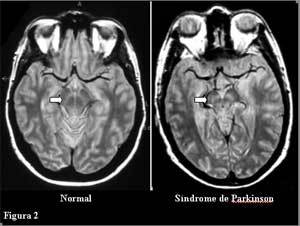

• La neuropsicología estudia las relaciones existentes entre la función cerebral y la conducta humana. Esta disciplina se basan el análisis sistemático de las alteraciones conductuales asociadas a trastornos de la actividad cerebral, provocados por enfermedad, daño o modificaciones experimentales.